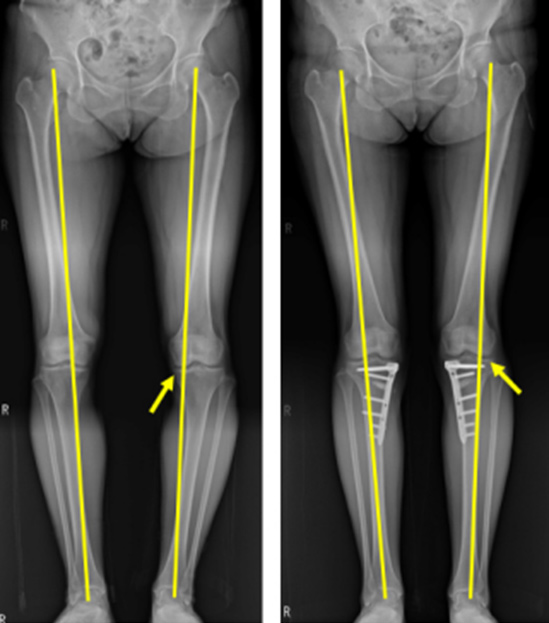

O자로 휜 다리는 방치할 경우 무릎 관절염으로 이어질 우려가 크고 장기간 지속되면 골반과 허리에도 무리가 되어 척추 질환을 유발하기도 합니다. 고관절 중심에서 발목 중심을 이은 선을 하지의 축이라고 하는데 보행시 체중이 가해지는 선입니다. 축이 무릎의 중앙이 아닌 안쪽을 지나게 되고 무릎 안쪽이 체중 부하를 많이 받아 관절연골이 손상되고 관절 간 간격도 좁아지면서 퇴행성 관절염이 발생하기 쉽습니다.

하지의 축을 내측에서 외측으로 옮겨주어 손상되지 않은 건강한 바깥쪽 연골에 체중을 더 부과시켜 관절염을 치료하는 ‘경골근위부절골술’이 효과적입니다. 이 수술은 흔히 ‘휜다리 교정술’이라고도 부르는데 휜 다리를 교정함으로써 관절염을 치료하는 수술법으로 주로 60세 미만의 활동적인 환자에게 적합하며 인공관절없이도 관절염의 치료가 가능하며 다리 모양 또한 일자로 바르게 바뀌어 환자들의 만족도가 큰 치료법입니다.